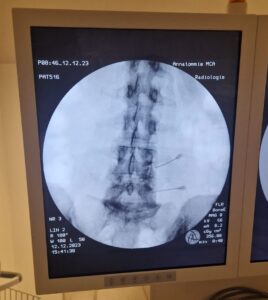

Dit proces heb ik een aantal jaar vol kunnen houden. Tot de pijn mij afgelopen jaar zo ontzettend hinderde en ik me volledig moest ziekmelden van mijn werk. Ik heb de specialist huilend gesmeekt om mij verder te helpen, omdat ik geen kwaliteit van leven meer had op die manier. Na hernieuwde MRI onderzoeken bleek dat er niet alleen een cervicale stenose (zenuwvernauwing) tussen nekwervels C5 en C6 aanwezig was, helaas bleek er inmiddels ook een stenose tussen de wervels C6 en C7.

De pijn die ik had was dus niet heel erg vreemd. Na het afgelopen jaar 4 keer een zenuwblokkade te hebben geprobeerd, welke uiteindelijk alleen niet mochten baten. Zat er volgens de specialist nog meer 1 ding op: opereren en zorgen dat ik zo snel mogelijk weer grip op mijn leven zou krijgen.

Operatie

Én op dat punt ben ik nu 26 maart ben ik geopereerd aan de cervicale stenose tussen nekwervels C6 & C7. Nu maar hopen dat dit voldoende resultaat mag gaan hebben en de pijnklachten gaan afnemen. De operatie is mij 100% meegevallen.